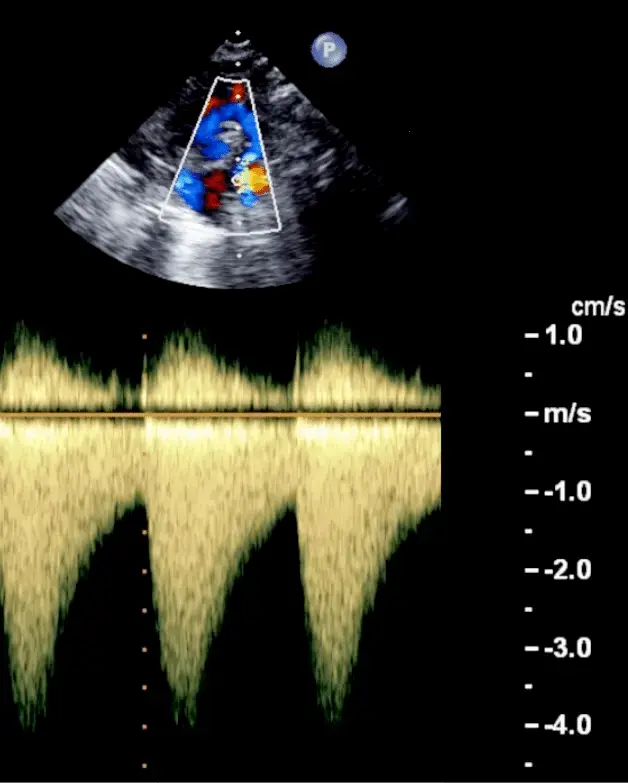

Echo for Valvular AS

- Cannot tell severity of stenosis with 2D-echo alone. You will need Doppler to help determine severity of AS.

- Aortic velocity is measured using continuous-wave doppler ultrasound with examination from multiple acoustic windows

- Mean gradient is calculated by averaging instantaneous gradients over the systolic ejection period using the modified Bernoulli equation,

Underestimation due to improper Doppler alignment across the Aortic Valve

If not parallel to the AS jet, you will not get the highest mean AV gradient or peak velocity across the AV → underestimate severity of AS. Importantly, you cannot overestimate the gradient (Exceptions: significant anemia or Subaortic Stenosis).

- Doppler assessment

- Measurements required

- LVOT diameter (2D)

- LVOT velocity, TVI (PW Doppler)

- Peak AV velocity, TVI (CW Doppler)

- Aortic valve area (AVA)

- Continuity equation valve area:

- Requires 3 measurements:

- AS jet velocity (CW Doppler),

- LVOT diameter to calculate cross-sectional area (CSA), and

- LVOT velocity (PW Doppler)

- The above figure is from the Mayo Echo Boards video where the presenter highlights the importance of calculating the AV TVI in multiple windows to ensure you are appropriately calculating the highest VTI and avoid miscalculation/miscalssification. In Thaden et al (JASE, 2015), the authors found that peak velocity was found outside of the apical window 61% of the time and that neglecting non-apical window misclassified AS 23% of the time.